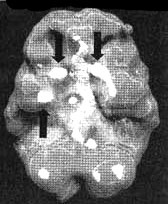

Заболевание Альцгеймера, разрушительная прогрессирующая форма старческого слабоумия, является одной из главных проблем с памятью у пожилых людей. К сожалению, у многих это заболевание крадет годы заслуженного отдыха, а их близких доводит до физического, эмоционального и финансового истощения. Действенным диагностическим методом в таких случаях оказывается SPECT. Прежде чем медикам стали доступны методы функциональной диагностики, единственным достоверным способом поставить этот диагноз было вскрытие. Сканирование SPECT показывает типичное для болезни Альцгеймера снижение перфузии в обеих височных долях и снижение активности в теменных долях. Иногда такая картина возникает за три-шесть лет до появления симптомов. Некоторые новые препараты для лечения этого заболевания, похоже, могут приостанавливать его развитие. В ходе сканирования мы наблюдали, что благодаря их действию улучшается перфузия в тех частях мозга, которые отвечают за память и мышление, в том числе и в височных долях. На иллюстрациях представлен мозг больного синдромом Альцгеймера, который стал забывчивым, часто не мог найти дорогу, когда выходил из дома, стал забывать элементарные вещи, например разучился самостоятельно одеваться и стал проявлять все больше агрессии по отношению к собственной жене. Мозг Хэрриет. Последствия энцефалита ![]() Трехмерное изображение нижней поверхности. Обратите внимание на выражений сниженную активность в обеих височных долях (см. стрелки). Болезнь Альцгеймера ![]() Трехмерное изображение поверхности, вид сверху. Обратите внимание на выраженно сниженную активность в теменных долях (см. стрелки). ![]() Трехмерное изображение нижней поверхности. Обратите внимание на выраженно сниженную активность в височных долях (см. стрелки). Говорят, что «спазмами височных долей» страдал Федор Иванович Достоевский. Он считал свою болезнь «святым переживанием». Один из его биографов, Рене Фюлеп-Миллер, цитирует высказывание Достоевского, что эпилепсия «вызывает во мне чувства, о которых я доселе не подозревал, сообщая мне ощущения блаженства, изобилия и вечности». В своем романе «Идиот» Достоевский пишет: «Он задумался между прочим о том, что в эпилептическом состоянии его была одна степень почти пред самым припадком (если только припадок приходил наяву), когда вдруг, среди грусти, душевного мрака, давления, мгновениями как бы воспламенялся его мозг, и с необыкновенным порывом напрягались разом все жизненные силы его. Ощущение жизни, самосознания почти удесятерялось в эти мгновения, продолжавшиеся как молния. Ум, сердце озарялись необыкновенным светом; все волнения, все сомнения его, все беспокойства как бы умиротворялись разом, разрешались в какое-то высшее спокойствие, полное ясной, гармоничной радости и надежды, полное разума и окончательной причины. Но эти моменты, эти проблески были еще только предчувствием той окончательной секунды (никогда не более секунды), с которой начинался настоящий припадок. Эта секунда была, конечно, невыносима. Раздумывая об этом мгновении впоследствии, уже в здоровом состоянии, он часто говорил сам себе, что ведь все эти молнии и проблески высшего самоощущения и самосознания, а стало быть и „высшего бытия“, не что иное как болезнь, как нарушение нормального состояния, а если так, то это вовсе не высшее бытие, а, напротив, должно быть причислено к самому низшему. И однако же, он все-таки дошел наконец до чрезвычайно парадоксального вывода: „что же в том, что это болезнь?“, решил он наконец, „какое до того дело, что это напряжение ненормальное, если самый результат, если минута ощущения, припоминаемая и рассматриваемая уже в здоровом состоянии, оказывается в высшей степени гармонией, красотой, дает неслыханное и негаданное дотоле чувство полноты, меры, примирения и встревоженного молитвенного слития с самым высшим синтезом жизни?“». Брайс Льюис Кэрролл, по некоторым свидетельствам, тоже страдал «явлениями от височных долей», которые хорошо отражены в зрительных образах Алисы в его книге «Алиса в стране чудес». Семилетний Брайс, которому мать стала читать «Алису», очень разволновался. Он сказал, что чувствует себя как Алиса. «Со мной происходят странные вещи, — рассказал он матери. — Я вижу всякие вещи». Среди бела дня он наблюдал, как предметы меняют свою форму, часто уменьшаясь в размерах. Ночью он видел зеленоватых призраков. У Брайса обнаружилось много симптомов тревожности. Его мать, перепугавшись, что Брайс «сходит с ума» (а его двоюродному брату поставили диагноз «шизофреноподобное состояние»), мать привела его ко мне на прием. Услышав о его симптомах, я заподозрил, что одна или обе височные доли у него гиперактивны. Сканирование SPECT выявило нарушения в правой височной доле и повышенную активность базальных ганглиев. Я назначил Dapakote (противосудорожный препарат, эффективный при лечении поражений височных долей), а также сеансы психотерапии для снижения тревожности. В течение двух недель странные состояния Брайса прекратились, а в течение полугода снизилась и тревожность. Мозг Брайса. Эпилепсия височных долей ![]() Трехмерное изображение нижней поверхности. Обратите внимание на область повышенной активности в глубоких отделах правой височной доли (стрелка снизу вверх) и базальных ганглиях (стрелки вниз). Эллен и Джек У Эллен и Джека похожие истории болезни. Оба были слегка замкнутыми. У обоих случались приступы головокружения и беспричинной паники. У обоих религиозный опыт занимал довольно значительное место в жизни. У Эллен (32 года) глубокие религиозные переживания практически парализовали ее жизнь. Она не могла работать и находилась в социальной изоляции. Джека очень заинтересовали ее «периоды глубокого духовного просветления», но он никак не мог понять, что это означает. Ко мне на прием Эллен привели ее родители, которых беспокоила ее социальная изолированность. Джек хотел обследоваться по поводу приступов паники. В обоих случаях сканирование выявило выраженную гиперактивность глубинных областей в височных долях. Значительная часть их симптомов ушла после того, как они начали принимать Depakote. При этом, продолжая прием этого препарата, оба остаются глубоко религиозными людьми. Правда, они больше не остаются погруженными в свои мысли значительную часть времени, как это было раньше. Джим Как в случае Эллен и Джека, Джима беспокоили приступы головокружения и панического страха. У него тоже бывали периоды «религиозных мыслей», во время которых он ощущал «присутствие дьявола», становился неуверенным и напуганным. Его страх перед дьяволом преследовал его, делал замкнутым. В семье считали, что он страдает паранойей. В результатах сканирования мозга Джима выявилось интересное отличие от результатов Эллен и Джека. У Джима нарушения обнаружились в левой, а не в правой височной доле. На основании своего опыта я полагаю, что нарушения именно в левой височной доле проявляются особенно негативными или мрачными мыслями. После того как Джим стал принимать Depakote, «присутствие дьявола» завершилось. |